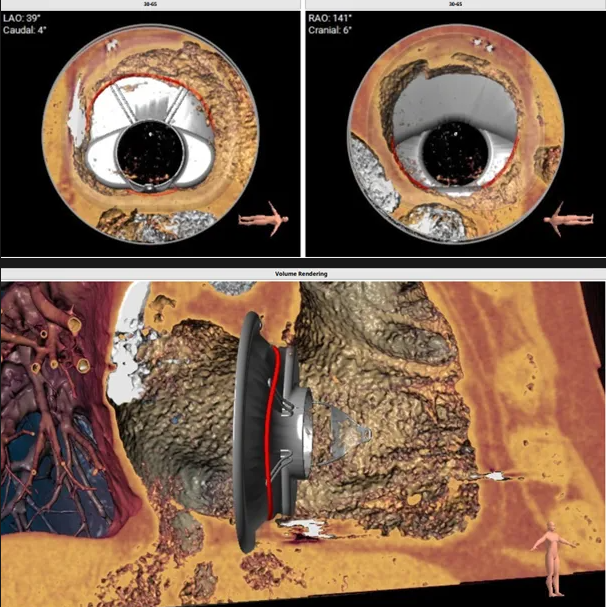

三尖瓣環(huán)切線位夾角 85°

瓣膜植入模擬